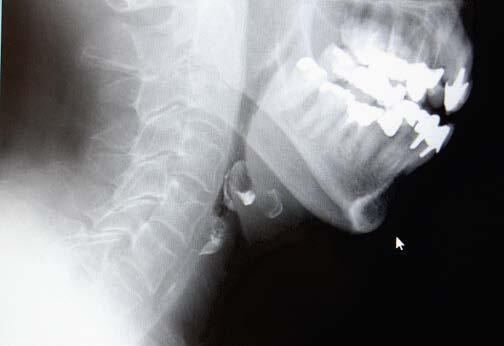

さらに詳細な嚥下状態を見る必要があると判断した場合、嚥下造影検査(VF)を行います。形態や量を変え、バリウムの入った検査食品を食べたり飲んだりして、リアルタイムに口から送り込まれていく様子をレントゲンで観察し、摂食嚥下チームで分析・評価を行います。そして、その人にあった「食事の形態」を提案し、その人にあった「リハビリ」を行います。

嚥下造影検査の様子

食道と気管の入口付近に残留物。